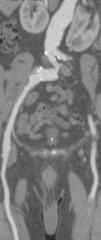

Objetivos. Evaluar la eficacia diagnóstica de la angiografía por tomografía computarizada multidetector (ATCM) en la arteriopatía de miembros inferiores (MMII), comparándola con angiografía por sustracción digital (ASD). Material y métodos. Se estudiaron 24 pacientes con arteriopatía de MMII. Se realizaron ATCM (4 detectores) y ADS realizando doble lectura entre las dos técnicas. Los territorios vasculares se dividieron para facilitar el análisis. Se calcularon sensibilidad (S), especificidad (E), prevalencia, valor predictivo positivo y negativo (VPP, VPN) y concordancia (test de Kappa). En arterias de tercera porción se estudió el rendimiento diagnóstico del ATCM realizando una curva ROC. Resultados. El estudio ATCM para la evaluación de la patología arterial mostró: una S menor en el estudio de la arteria ilíaca primitiva y arteria ilíaca interna (S: 0,65 y 0,71) con E de 0,94 y de 1; en los demás territorios vasculares obtuvimos S próximas a 1, disminuyendo algo la E. La concordancia fue muy alta (kappa entre 0,62 y 1) en todos los territorios estudiados. La ATCM mostró más longitud de vaso que la ASD. En la tercera porción el mejor rendimiento diagnóstico (ROC) se obtuvo en la lectura de vasos patológicos. Conclusión. La ATCM presentó alta fiabilidad en el estudio de la arteriopatía de MMII, con alta concordancia respecto a la ASD. En vasos tortuosos la ATCM visualiza mal las lesiones, en cambio en vasos rectos y en tercera porción el estudio con ATCM visualiza más segmentos vasculares.

Objectives. To evaluate the diagnostic efficacy of multidetector computed tomography angiography (MDCTA) in lower limb arteriopathy (LLA) by comparing it with digital subtraction angiography (DSA). Material and methods. Twenty-four patients with LLA were studied. All patients underwent MDCTA (four detectors) and DSA, with double reading between the two techniques. Vascular territories were divided to facilitate analysis. Sensitivity (S), specificity (Sp), prevalence, positive and negative predictive values (PPV, PNV), and concordance (Kappa test) were evaluated. In third-portion arteries, the diagnostic performance of MDCTA was evaluated using an ROC curve. Results. MDCTA study to evaluate arterial pathology showed: Lower sensitivity in the study of the internal iliac artery (S: 0.65 and 0.71) with Sp 0.94 and 1. In the other vascular territories, S approached 1, with a slight decrease in Sp. Concordance with DSA was very high (kappa between 0.62 and 1) in all of the territories studied. MDCTA showed greater vessel longitude than DSA. In the third portion, the best diagnostic performance (ROC) was obtained in the reading of pathological vessels. Conclusion. MDCTA was highly reliable in the study of LLA, with high concordance with DSA. In tortuous vessels, MDCTA depicted the lesions poorly; however, in straight vessels and third-portion vessels, MDCTA showed more vascular segments.